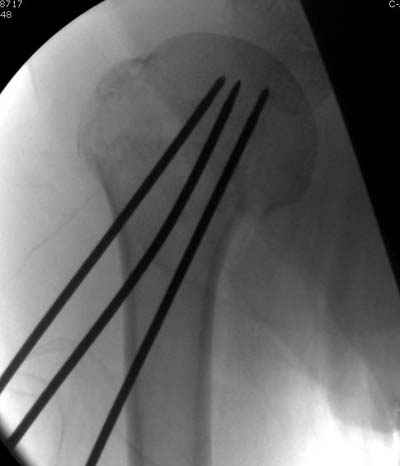

Спасибо за участие в дискуссии -перелом шейки плеча, для себя я прояснил многие технические моменты...

Посылаю послеоперационные Рг граммы.

Поздравляю, получилось просто замечательно. Если можно, расскажи чуть подробнее, как делали - как вправляли, как вводили спицы, поворачивали ли их?

Я и сам доволен результатом. В предпоследнем письме я кратко описал ход операции - закрыто репонировать не удалось( 2 недели с момента травмы и 1 неделя после неудачной репозиции) после удаления пучков спиц, пришлось сделать - 2см разрез на уровне перелома и с помощью периостального элеватора (золотое правило механики) *одеть* головку на дистальный отломок.

Спицы проводил через старые отверстия, вращая пучок импактором- направителем при его введении в головку.